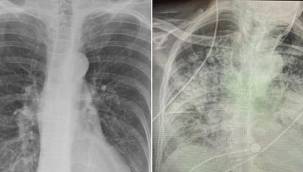

Coronanın korkunç etkisi ortaya çıktı: Sigara tiryakisinden kat kat daha kötü